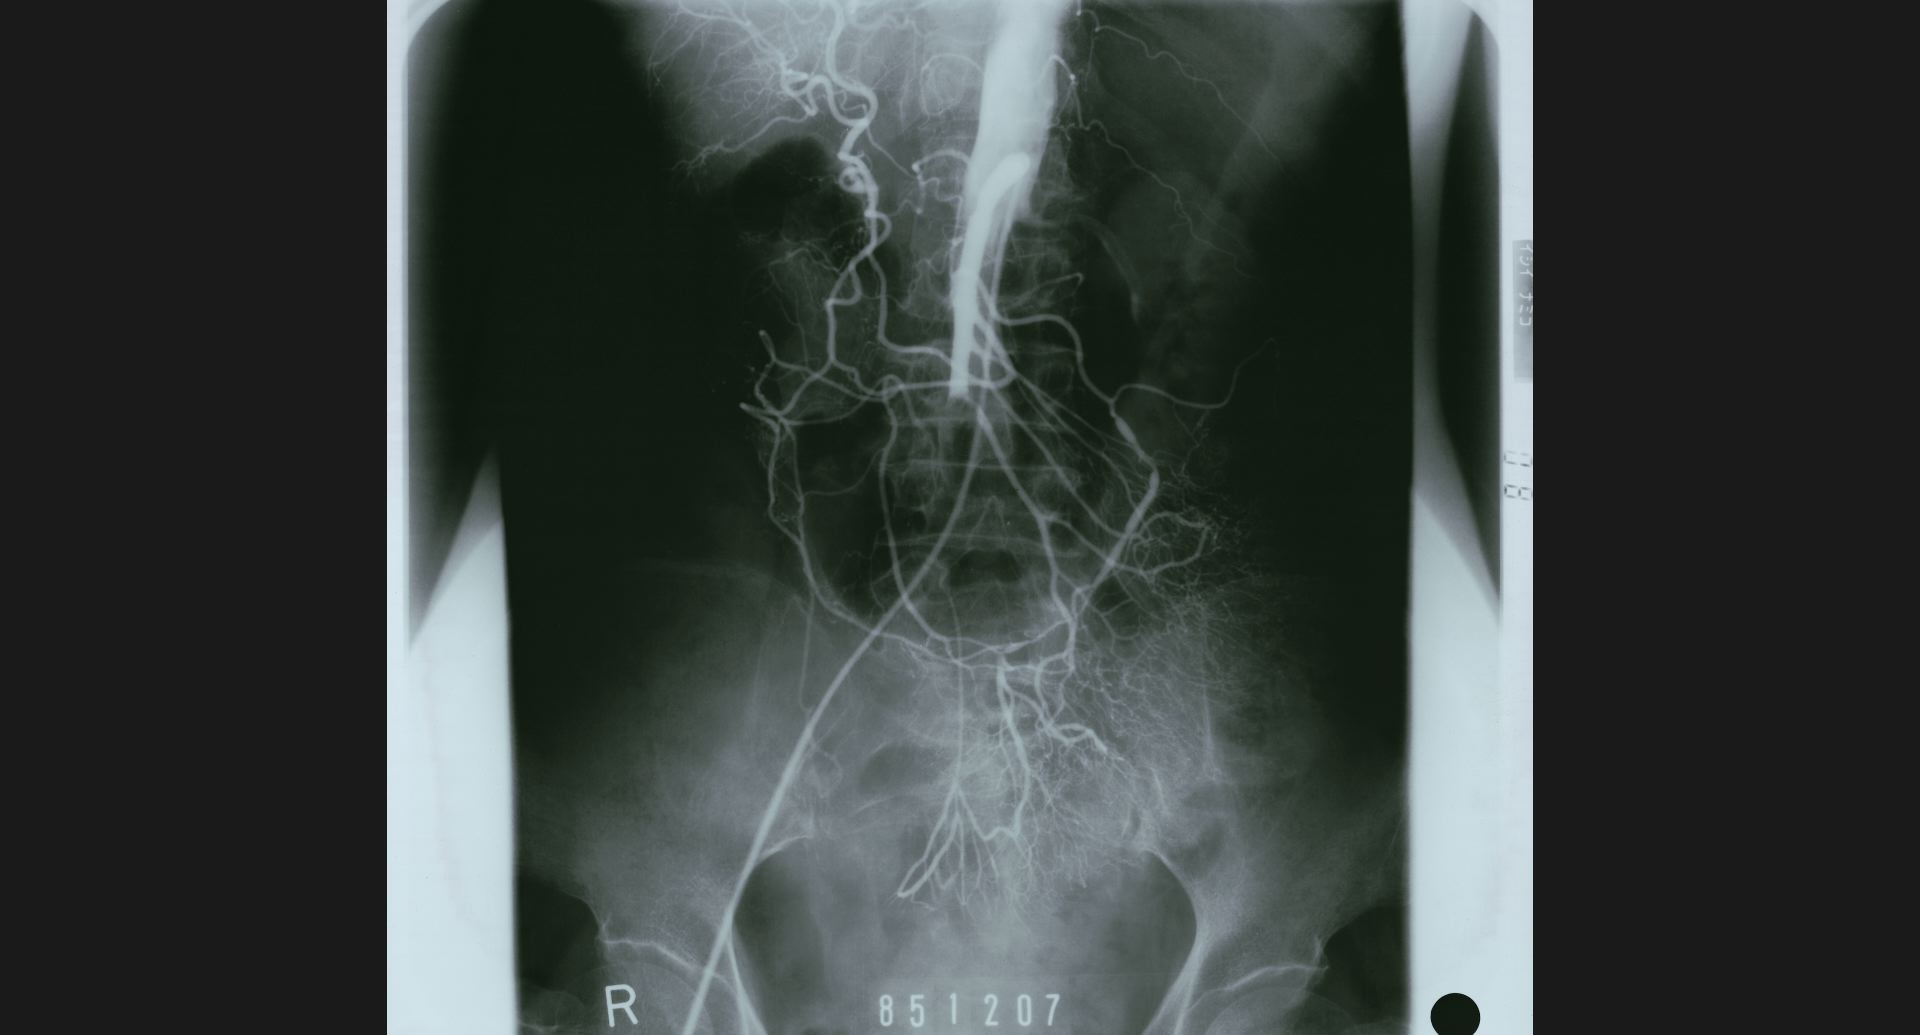

fig.10(99KB) :SMA thrombosis (angiography)

閉塞部位。腸管壁の細かい動脈。